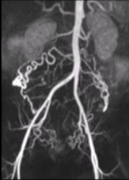

[子宫动脉栓塞时的卵巢动脉栓塞]

子宫动脉栓塞时的卵巢动脉栓塞

卵巢动脉供血 卵巢是子宫动脉供应的最常见另外一个来源。Nikolic B et alJVIR. 1999; 10: 1167-1170 卵巢动脉到子宫动脉的吻合类型 (A) I 型卵巢动脉与子宫动脉吻合。卵巢动脉在子宫肌瘤供应通过输卵管-卵巢段之前连接到子宫壁内动脉(箭头)。 (B)Il型卵巢...